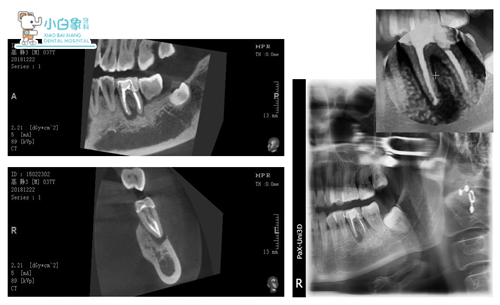

X线示:45根尖区类圆形暗影,边缘骨白线。36根管充填影像,欠填,尖端膨大。

ct确定手术切口及入口位置

CT定位后:龈缘下5mm行半月形切口,翻瓣,见骨缺后扩大,刮除,清创,截根,置骨粉盖膜,缝合。

术后X线检查